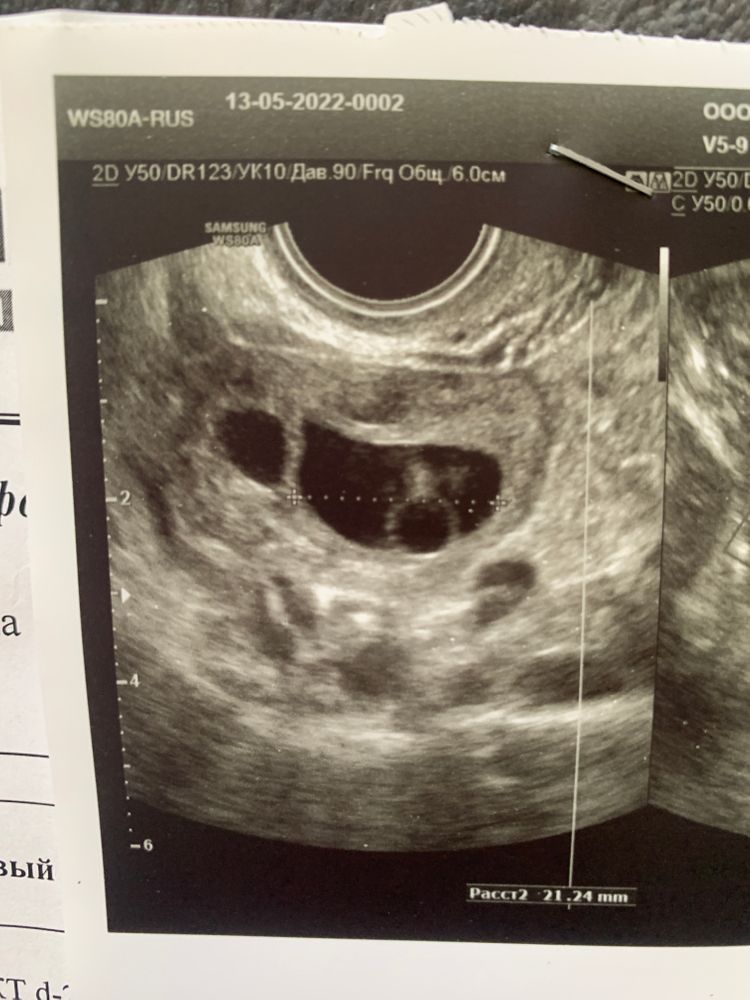

Это преовуляторный фолликул

То, что форма преовуляторная - видно, а вот есть в нем ЯК или нет - не узнать.

Разве по узи можно сказать пустой ли фолликул? На сколько я слышу, то это узнают после пункции

Ольча, вот я тоже самое знаю😑 ещё и форма странная сказала.